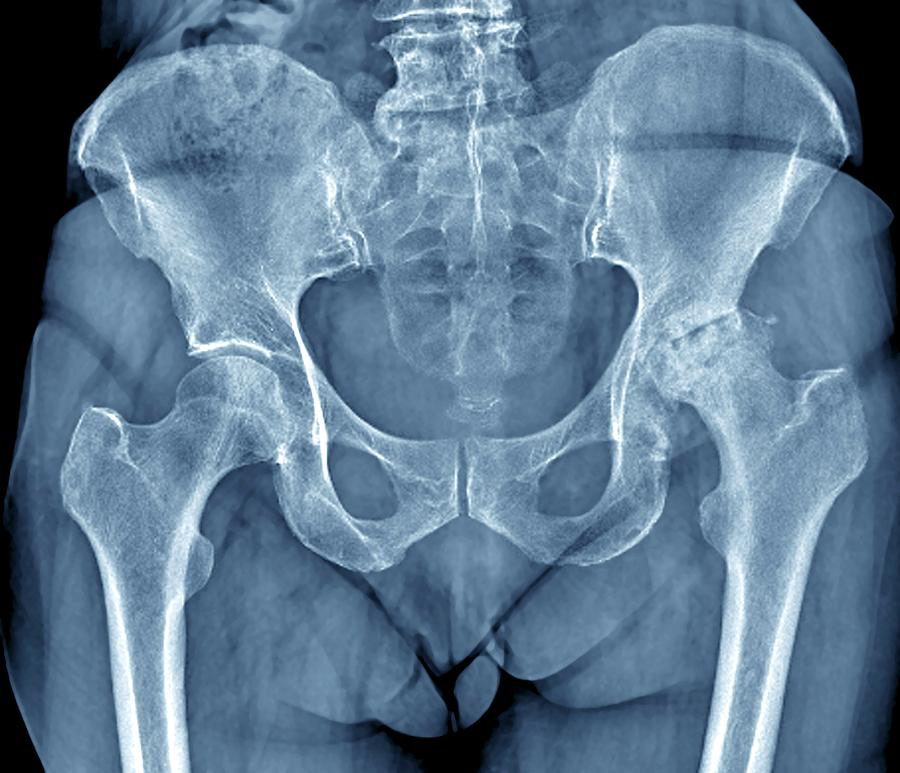

X Ray findings-LOSS

The classic radiographic features of OA are:

• Loss of joint space.

• Osteophyte formation.

• Subchondral sclerosis.

• Subchondral cysts.

Any classification you know?

The Kellgren-Lawrence (KL) Classification is a grading system used to assess the severity of osteoarthritis.

Kellgren-Lawrence Grading System for Osteoarthritis

Grade 1 (Doubtful OA)

- Doudtful osteophytosis.

Grade 2 (Mild OA)

- Definite osteophytosis.

Grade 3 (Moderate OA)

- Definite JSN.

Grade 4 (Severe OA)

- Deformity.